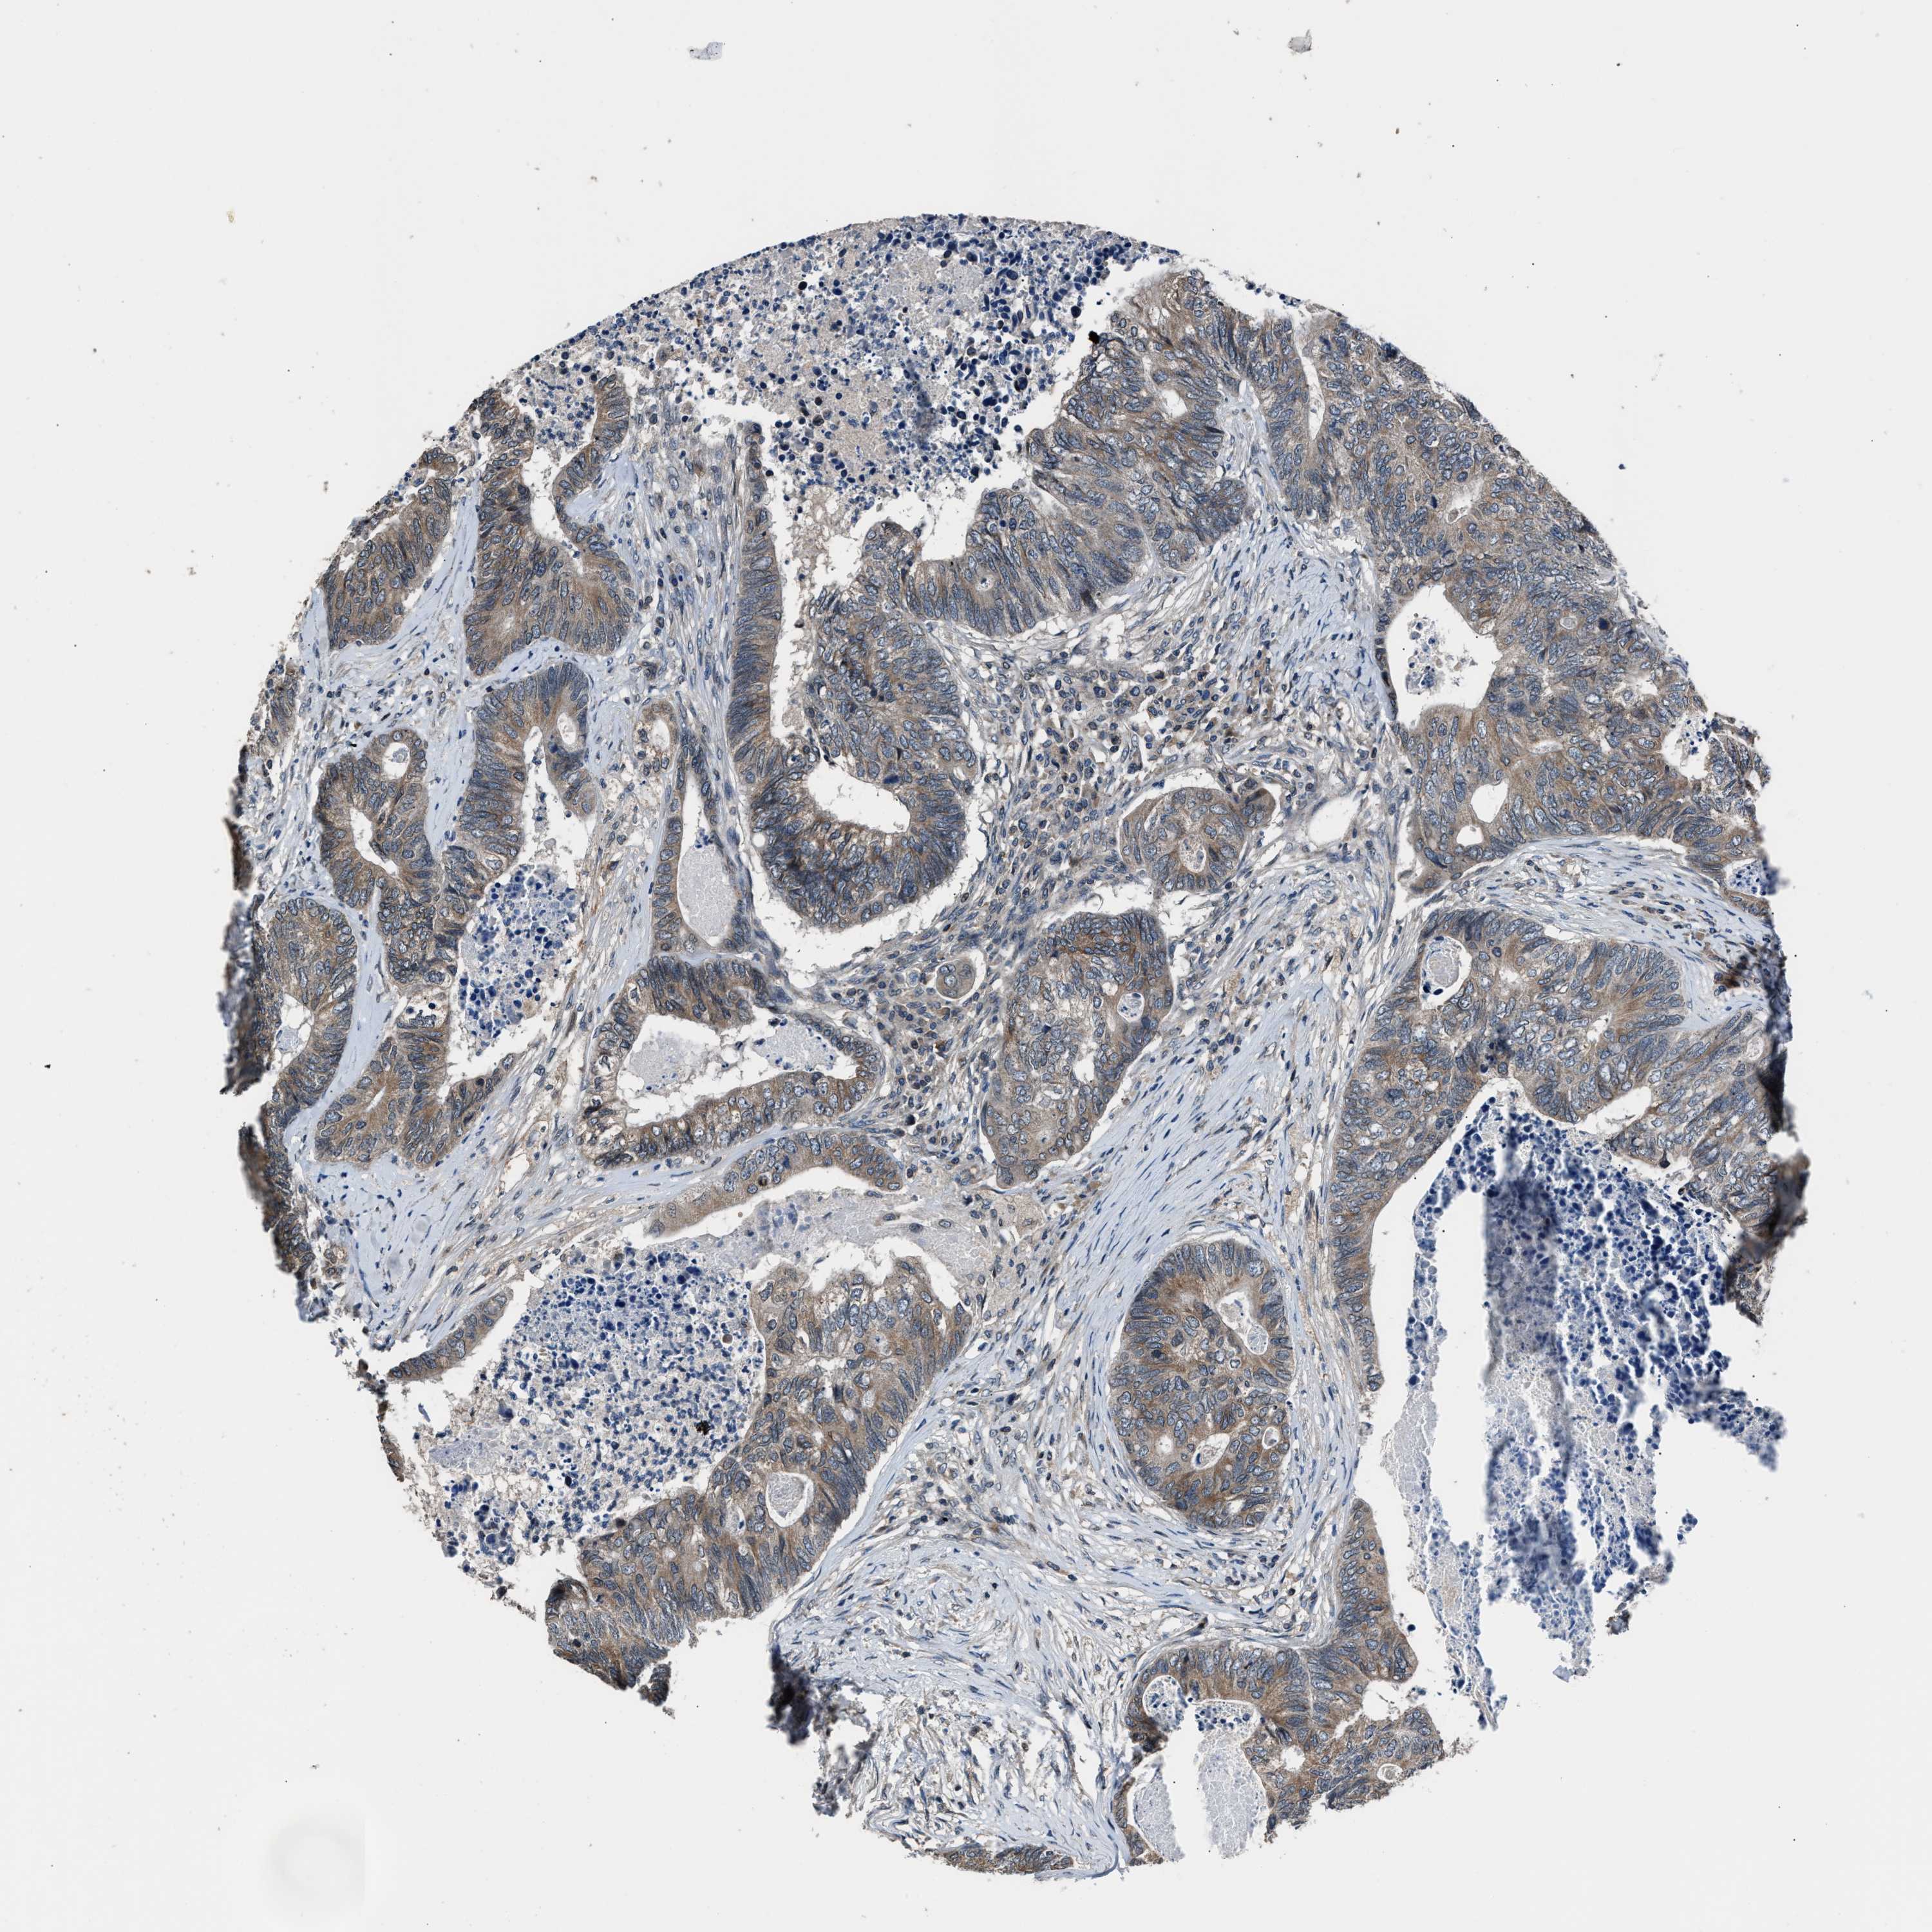

CANCER COLORECTAL CANCER Show tissue menu

Colorectal cancer

Human cancer

Colon adenocarcinoma